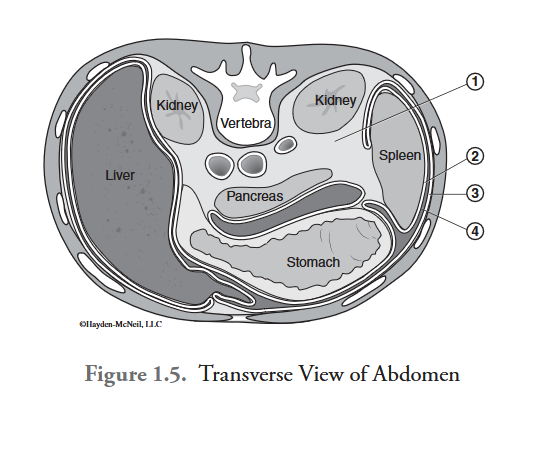

What is labeled #1?

retroperitoneal space

What is labeled #2?

visceral peritoneum

What is labeled #3?

parietal peritoneum

What is labeled #4?

peritoneal cavity